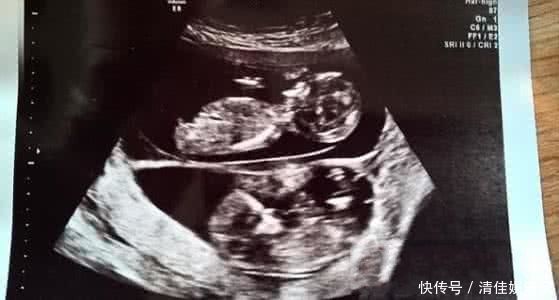

这一种古怪的表象叫异期复孕,就是孕妇在已经怀孕后卵巢又开释了一颗卵子。第二颗卵子也受精了,然后就一起怀上了两个宝宝。 从生理学上讲,这是不合情理的。孕期荷尔蒙通常会关闭女人的排卵体系,使她不行能在孕期排卵。正因为如此,异期复孕才这么令人震惊。

但异期复孕可能导致新胎儿早产、肺部出现问题。在经过检查之后,医生告知丈夫,格罗文伯格的两次受孕,存在这很大的问题。意思就是姐姐出生之后,弟弟可能还没有发育完整,可能出现一系列的先天性疾病。大千世界无奇不有,盘点那些解释不了的奇人、奇事、奇观、奇谈,欢迎大家和我一起挖掘身边的奇人异事,分享快乐和成果!